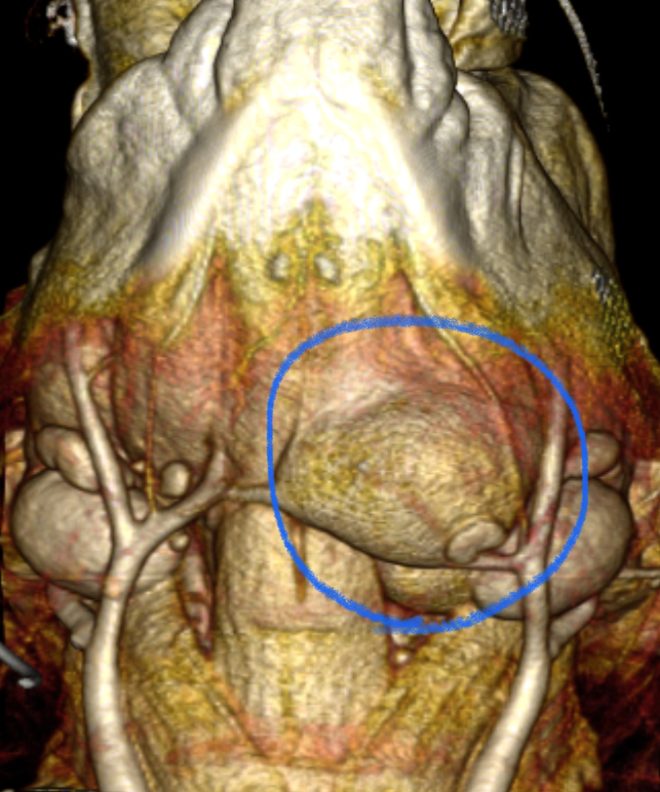

唾液は、唾液腺(下顎腺、舌下腺、頬骨腺、耳下腺)で作られ、導管を通って口の中に流れる消化液です。唾液瘤は、なんらかの原因による導管の損傷により唾液が周囲に漏出する疾患です。通常は無症状ですが、部位によっては気道を圧迫したり、飲み込みづらくなったり、感染から敗血症になる事もあります。

外科的治療は、唾液瘤の切除と唾液腺の摘出を行います。

今回のワンちゃんは、CT検査で舌下腺との連続性が確認できたため、下顎腺と舌下腺と導管を切除しました。導管は顎舌骨筋を切開したり、舌神経をくぐらせたり、可能な限り先端まで切除しました。できるだけ先端まで切除することで、再発を防ぐ事ができます。